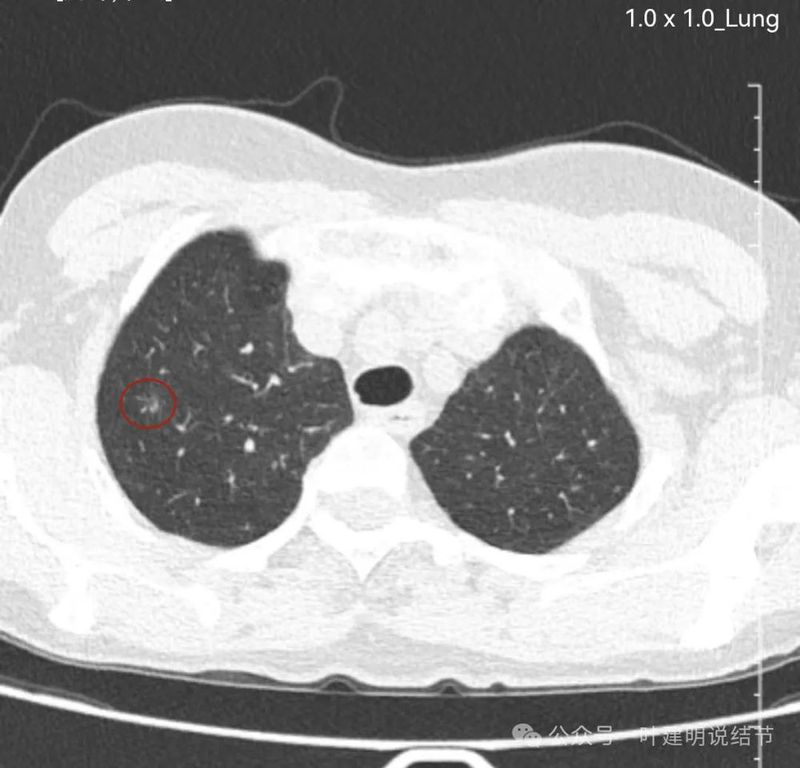

先来看两肺多发病灶的情况:

右上轮廓稍模糊结节,更像少许炎性改变。

右上混合密度结节,有血管进入,有实性成分,磨玻璃部分轮廓与边界清,与恶性较为符合,浸润性腺癌可能性较大点。当然由于首次发现,先抗炎后再复查更为稳妥些,有时炎性也会边界较清的。